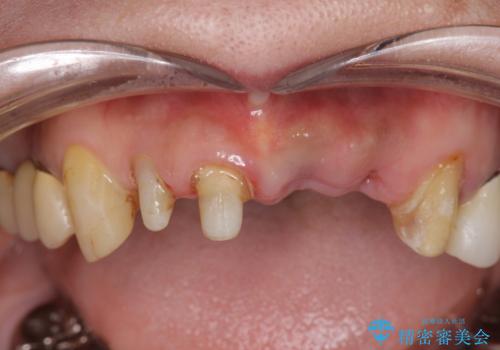

- 歩行中に躓いて転倒し、前歯2本がグラグラになってしまい痛み・審美性の改善を求めて来院されました。

X線検査・視診より強くぶつけた前歯は折れてしまい、抜歯が必要な状況です。

元々の噛み合わせが深く(ディープバイト)、転んで顎を強打したことで上顎前歯2本が根元から折れてしまい抜歯をしなければいけない状況となってしまいました。